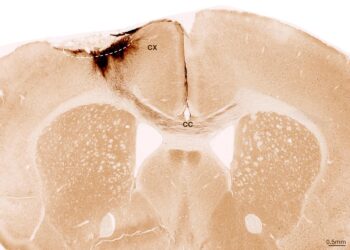

Read moreThis picture reveals a coronal part by way of the mouse mind after stroke and neural ...